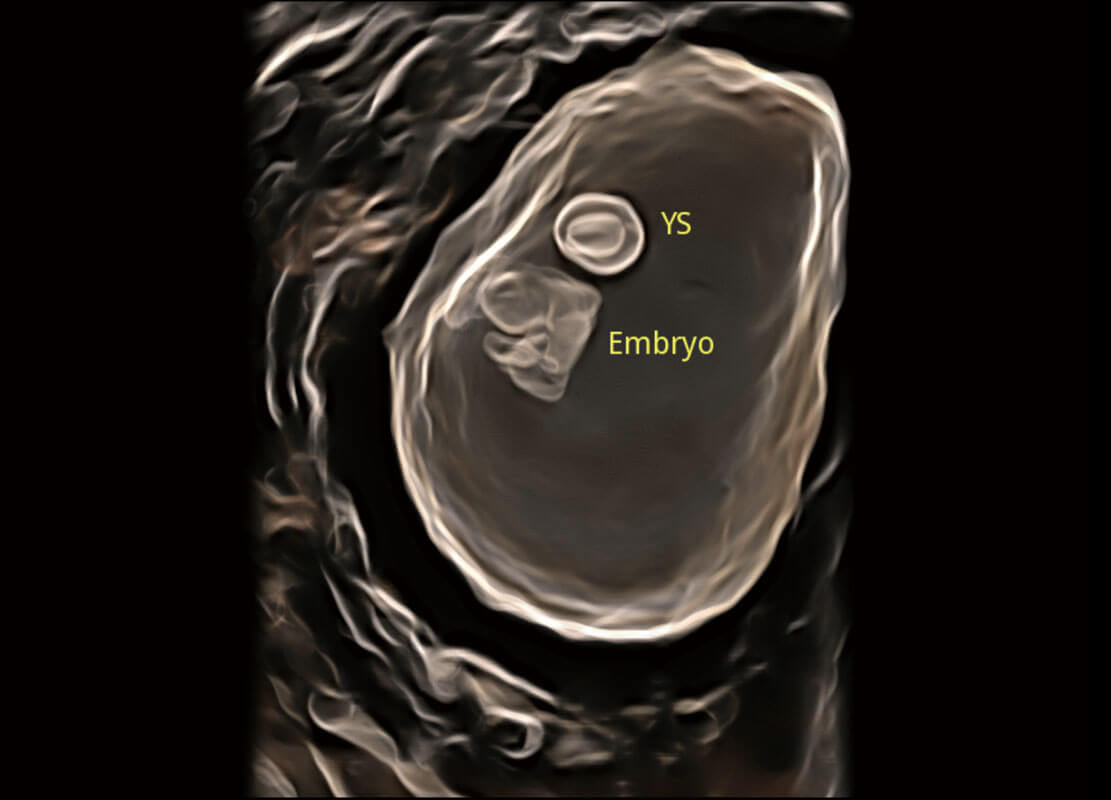

P60在胎兒早孕期超聲篩查中為您帶來(lái)優(yōu)異的圖像質(zhì)量。

高分辨率容積成像-早孕胎兒

光影成像-孕囊